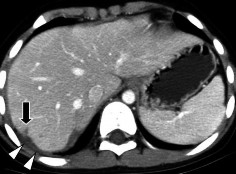

Hình 1.17. CTG độ III. Tụ máu góc dưới thùy gan phải (mũi tên) > 10cm.

Hình 1.18. CTG độ III. Rách nhu mô gan > 3cm thùy gan phải, chảy máu.

Nguồn: Shanmuganathan K, Mirvis SE [21].

Hình 1.19. CTG độ IV. Rách nhu mô

> 50% thùy gan phải.

Hình 1.20. CTG độ IV, rách nhu mô nhiều hạ phân thùy gan T.